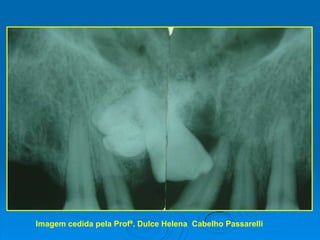

ODONTOMA COMPOSTOImagem cedida pela Profª. Dulce Helena  Cabelho Passarelli